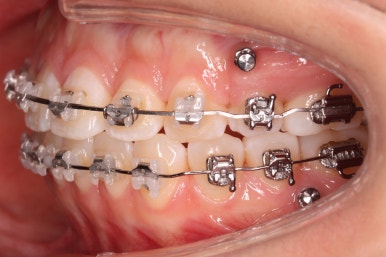

윗니는 발치를 했고, 잇몸뼈에 미니스크류를 식립하여 앞니를 뒤로 당겨넣고 있습니다.

이 뽑은 틈은 거의 없어져가고 있고, 중간평가 이 후 더 필요한 위치에 미니스크류를 추가하여 당기고 밀고 밀어넣고 다양한 작업을 해주게 됩니다.

틈은 다 다물어졌고, 부가적인 정교한 마무리 과정을 더 거치게 됩니다.

중앙선도 잘 맞고 교합도 잘 마무리되었습니다.

이 뽑은 자리가 다시 벌어지지 않게 앞니가 다시 틀어지지 않게 유지철사를 부착하고 마무리를 하였습니다.